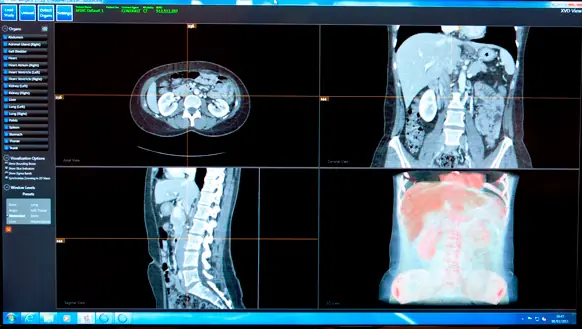

Una nueva herramienta de búsqueda desarrollada por investigadores de Microsoft indexa imágenes médicas del cuerpo humano, en lugar de páginas web. En imágenes de TC, éste encuentra automáticamente órganos y otras estructuras para ayudar a los médicos a navegar y trabajar con imágenes médicas en 3-D.

Los dispositivos de TC utilizan los rayos X para capturar muchas secciones del cuerpo que pueden ser combinadas para crear una representación en 3-D de él. Se trata de una poderosa herramienta para el diagnóstico, pero está lejos de ser fácil de navegar, señala Antonio Criminisi, quien lidera un grupo en Microsoft Research, con sede en Cambridge, Reino Unido, que está tratando de cambiar eso. "Es muy difícil, incluso para alguien muy capacitado, llegar al lugar que tiene que examinar para encontrar el origen de un problema", afirma él.

Cuando se carga una imagen al software de Criminisi, el programa indexa los datos y enumera los órganos que ha encontrado en el lateral de la pantalla, creando una tabla de hipervínculos para el cuerpo. Un usuario puede hacer clic en, por ejemplo, la palabra "corazón" y se le presentará con una vista clara del órgano sin tener que navegar a través de las imágenes manualmente.

Una vez que un se ha encontrado un órgano de interés, al usuario se le muestran dos vistas, una 2-D y una 3-D mejorada, de las estructuras en la zona, y éste puede navegar por la zona tocando la pantalla en la que se muestran las imágenes. La nueva imagen también puede ser automáticamente y perfectamente comparada con otra anterior del mismo paciente, por lo que es fácil ver cómo una enfermedad ha progresado o retrocedido.

El software de Criminisi utiliza el patrón de luz y oscuridad en la imagen para identificar estructuras en concreto; el programa fue desarrollado mediante el entrenamiento con algoritmos de aprendizaje para reconocer unas características determinadas utilizando cientos de imágenes en las que los expertos habían marcado los órganos principales. La indexación de un nuevo análisis sólo toma un par de segundos, destaca Criminisi. El sistema fue desarrollado en colaboración con médicos del Hospital Addenbrookes de Cambridge, Reino Unido.